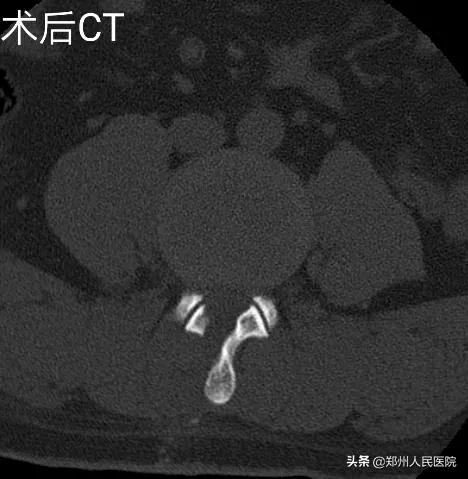

为刘叔进行的“单侧双通道UBE脊柱内镜术”在不足两个小时后顺利结束,术中麻醉效果极佳,出血量只有数十毫升,清晰放大的视野下,突出的髓核及增厚的黄韧带完全摘除,骨性狭窄磨钻安全扩大减压,偶尔出现的小出血点也在射频刀头的控制下立即止血,轻松漂浮的神经根又重新出现了。

UBE技术即单侧双通道内镜技术(Unilateral Biportal Endoscopy Technique),利用多裂肌与棘突间的潜在间隙形成三角式的对流关系以保持良好灌注冲洗获取清晰术野,适用于颈、胸、腰椎退行性病变。

相对于发展比较成熟的椎间孔镜技术及后路椎板间入路单通道内镜技术,该技术通常建立两个通道,一个为观察通道,一个器械操作通道。